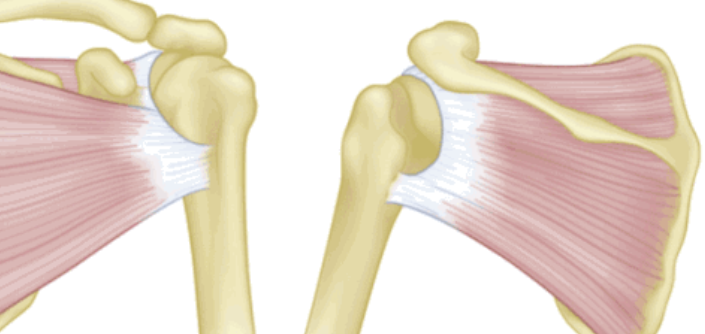

全层撕裂按照范围分为小撕裂:撕裂口<1cm,中撕裂:撕裂口1-3cm,大撕裂:撕裂口3-5cm,巨大撕裂:撕裂口>5cm。高清晰度的MRI是可以测定撕裂范围的。

按照撕裂的形状又分为新月形撕裂、U形撕裂、L形撕裂、倒L形撕裂、巨大回缩性/不可移动性撕裂。想要判断损伤的形状需要在MRI上利用多个平面、多张照片来分析。